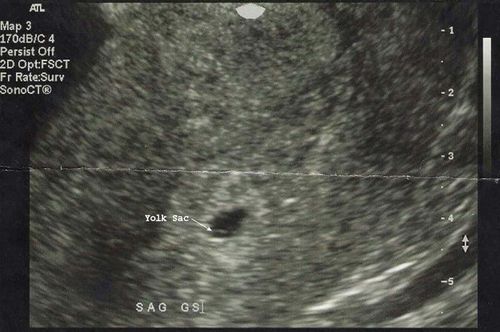

Có túi thai nhưng chưa có yolksac và phôi, liệu thai có đang phát triển không?

Cho em hỏi em trễ kinh 14 ngày, đi siêu âm thì có túi thai 6.3mm. 1 tuần sau em siêu âm lại thì túi thai 7.5mm. Em có bị ra ít huyết. Ra ít mà kéo dài đến nay là 3 ngày. Em đi khám 1 chỗ thì nói là thai sớm và thai bình thường. Qua hôm sau em ra phòng khám tư bác sĩ nói bị bong tróc túi thai 8.5mm. Em đã trễ kinh 25 ngày mà chưa có yolksac và phôi là không bình thường. Có nguy cơ thai ngừng phát triển. Cho em hỏi là có túi thai nhưng chưa có yolksac và phôi, liệu thai có đang phát triển không?